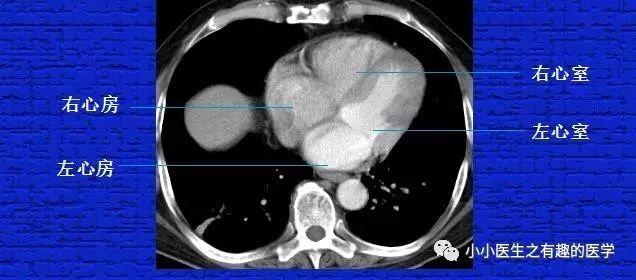

8.要知道左心室、右心室,这是划分肺段的主要依据之一。